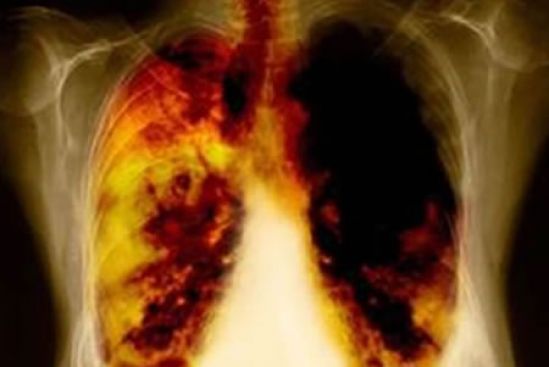

Es necesario emprender acciones para ayudar a disminuir la tasa de mortalidad, pues de acuerdo con la Organización Mundial de la Salud (OMS), es estima que entre el 30% y 50% de los casos de cáncer se pueden evitar. Y, aunque el cáncer de pulmón tiene una relación estrecha con el tabaquismo, existe un alto porcentaje de pacientes con cáncer de pulmón, cuya enfermedad no está asociada a esta adicción, como lo indica el Instituto Nacional de Cancerología (INCan): 45% de los pacientes de cáncer de pulmón nunca ha fumado, de ellos 67% son mujeres.

Todo ello reafirma la necesidad de una detección y tratamiento oportuno y adecuado para elevar la posibilidad de recuperación de los pacientes con cáncer de pulmón. De ahí la urgente necesidad de que todos los involucrados en la lucha contra el cáncer trabajen en conjunto para ayudar a reducir los altos índices de mortalidad por cáncer de pulmón en el país. Incrementar la esperanza de vida de los pacientes que ya padecen este terrible mal no es imposible.